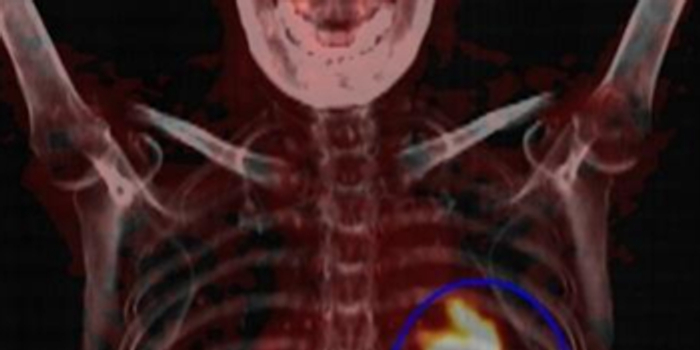

检查前,医护人员把一种名字叫氟代脱氧葡萄糖(18F-FDG)的显像剂注射到李阿姨的体内。这种显像剂是葡萄糖的类似物,与葡萄糖的具有相似的代谢途径,但不提供能量。这种显像剂的半衰期仅有109分钟,很快从体内代谢掉。在注射后候诊室经过一段时间的安静等待后,这种显像剂可以“点亮”人体内部的肿瘤病灶,通过PET/CT扫描就能把这些病灶显示出来(图1)。

图1:蓝圈内为“点亮”病灶